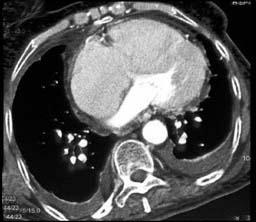

问题 男,38岁,反复咳嗽、咳痰伴发热15年余,痰结核菌素试验(—),结合CT图像,最可能的诊断是 ( )

选项 A.肺癌 B.肺结核 C.肺结节病 D.肺转移瘤 E.肺淀粉样变性

答案 E